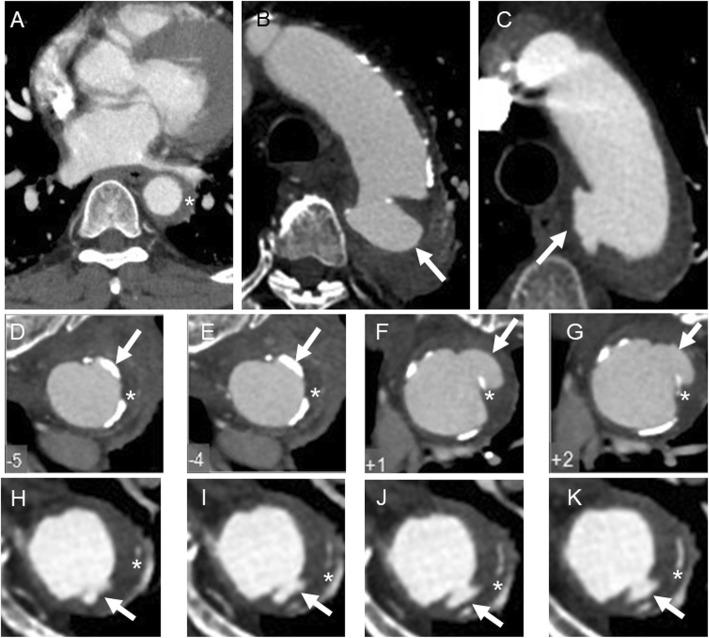

Aortic intramural hematoma (IMH) is a subset of acute aortic syndrome, and its prognosis may differ between races. This study aimed to study the prognosis of Chinese type B IMH patients and to find out risk factors.

A total of 71 type B IMH patients with or without penetrating atherosclerosis ulcer (PAU) administrated in our center between September 2013 and October 2017 were retrospectively studied. Both clinical and imaging data were collected and analyzed. The primary end point was aorta-related death, and the secondary end point was progression, which was defined as enlargement of aorta, increased aortic wall thickness, and aortic dissection or aneurysm formation. Kaplan-Meier survival analysis and Cox regression analysis were used for prognostic analysis.

Among these 71 patients, 21 had simple type B IMH, when 50 had type B IMH in association with PAU. Twenty-five patients received optimal medical therapy (OMT) alone, while 46 patients received surgery and OMT. The mean follow-up time was 27.5 ± 13.5 months. For type B IMH patients, association with PAU indicated poor prognosis and required more intensive management (HR = 16.68, 1.96141.87), while maximum aortic diameter (MAD) was an independent risk factor (HR = 1.096, 1.0161.182). For patients with PAU-IMH, MAD was an independent risk factor (HR = 1.04, 1.0211.194), while surgical treatment was independent protective factor (HR = 0.172, 0.0420.696).

Association with PAU and MAD were independent risk factors for type B IMH patients. Surgery may improve the outcomes for type B IMH in association with PAU.